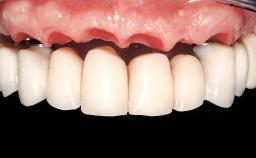

Immediate Loading of Six Implants in the Maxilla and Final Restoration with a Full-Arch Gold/Ceramic FDP Involving the Concept of Tilted Implants

Prosthesis Type FDP

Defining Characteristics Fully edentulous upper jaw to be rehabilitated with an implant-borne fixed dental prosthesis

Loading Protocol Immediate